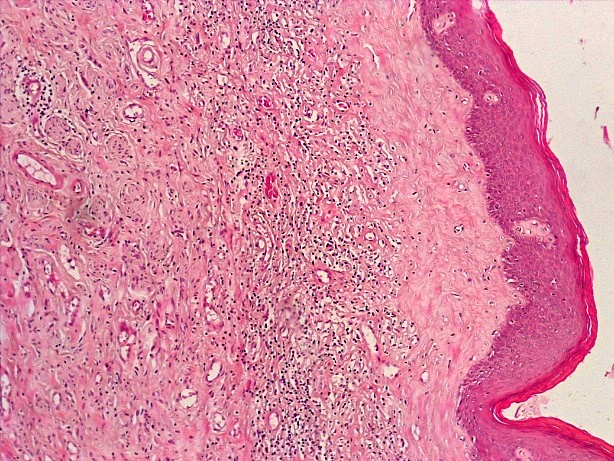

При проведении морфологического исследования тканей вульвы пациенток со склероатрофическим вариантом течения СЛВ также отмечалась резкая атрофия кожи за счет клеток эпидермиса и дермы, уменьшение клеточных слоев эпидермиса от 2–3 до 4–5 с участками повышенного ороговения (гипрекератоз). Количество базального слоя было снижено в разных случаях от 2–3 до 5–6 клеток в 1 мкм, что указывало на снижение функционального резерва эпидермиса. В случае длительного течения заболевания клетки базального слоя имели признаки дистрофии. В поверхностных слоях дермы отмечался фиброз с отложением масс гиалина, а также редукция кровеносных сосудов мелкого калибра, окруженных клеточным воспалительным инфильтратом из лимфоцитов и макрофагов (рис. 14–17).

Рис.16. Склероатрофический вариант течения СЛ. Неравномерная атрофия и гиперкератоз многослойного плоского эпителия, умеренновыраженное хроническое воспаление дермы с развитием фиброзной ткани (окраска гематоксилином-эозином, х100)

Fig.16. Scleroatrophic variant of the course of SL. Uneven atrophy and hyperkeratosis of the multilayer squamous epithelium, moderate chronic inflammation of the dermis with the development of fibrous tissue ((hematoxylin-eosin staining, x 100)